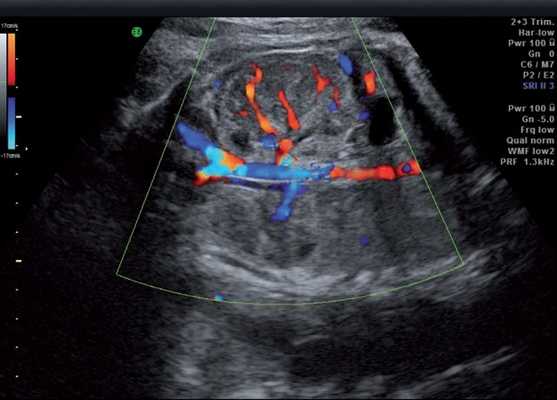

Под диафрагмой справа визуализировалось гиперэхогенное опухолевидное образование несколько неоднородной солидной структуры, с четкими ровными контурами, размером 50x38x35 мм. К нижнему полюсу данного образования прилежала правая почка, имеющая нормальные размеры, форму и структуру. Нижняя полая вена была смещена кпереди и влево. Обращала на себя внимание выраженная гепатомегалия, причем структура печени не была однородной. Она содержала множественные гиперэхогенные включения размерами до 17 мм, окруженные тонким гипоэхогенным периферическим ободком. Цветовое допплеровское картирование(ЦДК) демонстрировало интенсивную периферическую васкуляризацию опухоли (рис. 1-3).

Рис. 1. Нейробластома правого надпочечника плода. Беременность 31 нед 4 дня.

Рис. 2. Кровоток в нейробластоме плода. Цветовое допплеровское картирование. Отчетливо виден питающий сосуд, огибающий образование по его периферии. К нижнему полюсу образования прилежит интактная почка плода.